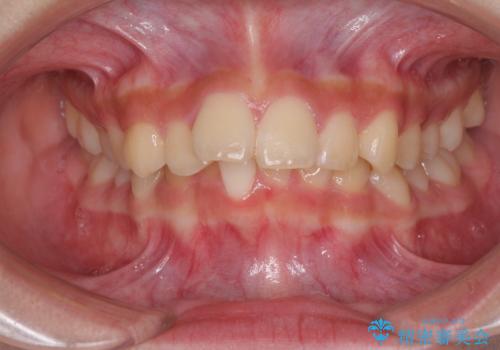

下の前歯が隠れてしまうほど深い咬み合わせ 高校生のインビザライン矯正治療

- 前歯の叢生と深い咬み合わせを気にして来院された患者様です。

奥歯の咬み合わせを見ると、上顎が下顎に対して相対的に前方にありました。